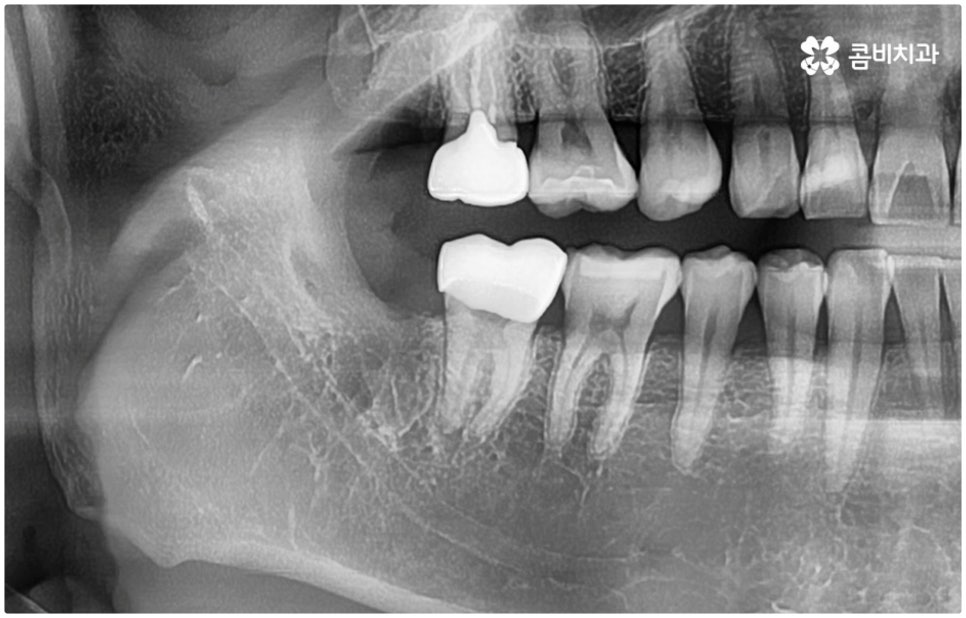

특히 매복 사랑니 중 잇몸 속에 전부 묻혀 있는 사랑니를 완전매복사랑니라고 부르는데 이 경우 누운 방향으로 자라나면서 앞 어금니 뿌리에 지속적인 압박을 가하여 신경을 누르기도 하고 치근을 흡수시키거나 치열이 앞쪽으로 쓰러지게 만들어 부정교합을 유발하기도 하며 드물게는 함치성 낭종이 생겨 턱뼈를 녹이는 상황까지 발생할 수도 있기 때문에 꼼꼼하게 검진을 하여 만약에 필요하다면 늦지 않게 발치 처치를 해 주어야 하는 거예요.

매복사랑니발치치과 를 선택할 때 어떤 것을 기준으로 고르는 것이 좋을까요? 사랑니가 완전히 매복되어 있다면 잇몸을 절개하고 상황에 따라 골삭제 후 치아를 조각내어 빼내줄 필요가 있는데 이러한 과정이 굉장히 까다롭기 때문에 먼저 환자분들의 사랑니 위치 및 뿌리의 형태, 인접 치아 구조, 주변 조직이나 신경 위치 등을 구체적으로 확인할 수 있는 3D CT와 같은 정밀 검진 장비를 갖추고 있는 매복사랑니발치치과 인지 체크해 보실 필요가 있어요.

하악 사랑니의 경우 하치조 신경을 건드리지 않도록 주의해야 하고 상악 사랑니의 경우 상악동 천공을 조심해야 하는데 이 때 환자분들의 상황 또한 개인마다 천차만별인 만큼 각각을 꼼꼼하게 살펴보고 섬세하게 발치 처치를 하기 위해 술자의 뛰어난 기술력 및 숙련도가 요구되므로 매복사랑니발치치과 의료진의 경력 사항을 면밀하게 살펴보시는 것도 도움이 될 거예요.